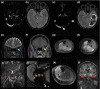

Results: In the study period 232,603 inhabitants from the main catchment area of our hospital (Rhein-Neckar-Kreis, county) received SARS-CoV-2 vaccinations. Twenty-one cases (new onset n = 17, flares n = 4) diagnosed a median of 11 days (range 3-23) following SARS-CoV-2 vaccinations (BNT162b2 n = 12, ChAdOx1 n = 8, mRNA-1273 n = 1) were identified. Cases included VITT with cerebral venous sinus thrombosis (n = 3), central nervous system demyelinating diseases (n = 8), inflammatory peripheral neuropathies (n = 4), myositis (n = 3), myasthenia (n = 1), limbic encephalitis (n = 1) and giant cell arteritis (n = 1). Patients were predominantly female (ratio 3.2:1) and the median age at diagnosis was 50 years (range 22-86). Therapy included administration of steroids (n = 15), intravenous immunoglobulins in patients with Guillain-Barré syndrome or VITT (n = 4), plasma exchange in cases unresponsive to steroids (n = 3) and anticoagulation in VITT. Outcomes were favourable with partial and complete remissions achieved in 71% and 24%, respectively. Two patients received their second vaccination without further aggravation of autoimmune symptoms under low-dose immunosuppressants.